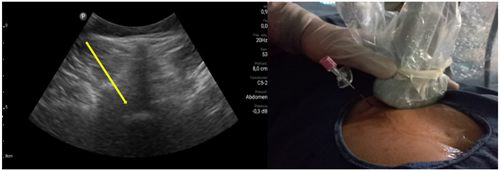

Pacientes y métodos: Un total de 25 pacientes con dolor radicular lumbosacro fueron seleccionados para recibir inyecciones epidurales interlaminares de esteroides en posición decúbito dorsal, utilizando la técnica ecoguiada en plano, en tiempo real, en eje corto o transversal. En todos los casos, un epidurograma de control fue realizado previo a la inyección de la solución de esteroides. El rendimiento de la técnica fue estudiado mediante la tasa de éxito de la misma, entendido como éxito a la obtención de un epidurograma sin necesidad de abandonar la técnica ecográfica en un tiempo menor a 10 minutos. El rendimiento del procedimiento fue estadísticamente evaluado por el método de la suma acumulativa (CUSUM), y la curva de aprendizaje aplicando este método fue construida.

Resultados: La distancia promedio desde la piel al complejo posterior evaluada por el escaneo ecográfico previo al procedimiento fue de 6,7 ± 1,8 cm. De los 25 procedimientos realizados, en 21 se alcanzó el espacio epidural sin ayuda de la fluoroscopia, en un tiempo promedio de 4,8 ± 1,2 minutos. Esto constituye una tasa de éxito del 84 %. En los cuatro procedimientos restantes el espacio epidural fue alcanzado con éxito mediante el uso complementario de la fluoroscopia.

Figura 1

Figura 2